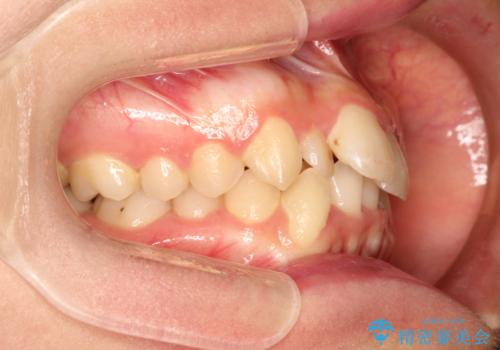

- 上下の全体的ながたつきが気になるとのことで来院されました。

上下左右の前から4番目の歯を抜歯をして、ワイヤー矯正にて並べる計画としました。

患者様が装置を早期に除去したいという希望もあり、少々下の前歯のがたつきが残った状態で矯正を終了しました。